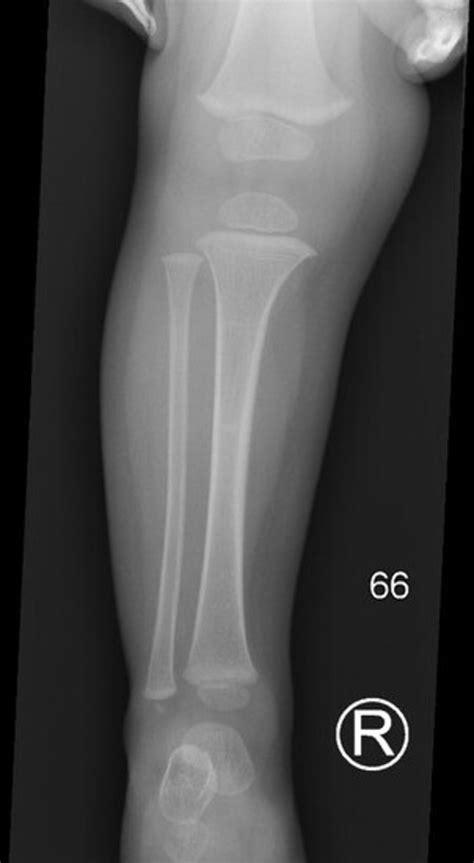

Discover the causes and symptoms of a painful lump by shin bone. Learn when to seek medical advice for potential shin injuries, bone cysts, or soft tissue swelling. Our expert guide helps you identify if your lower leg bump requires professional treatment, helping you understand your health concerns and path to recovery.